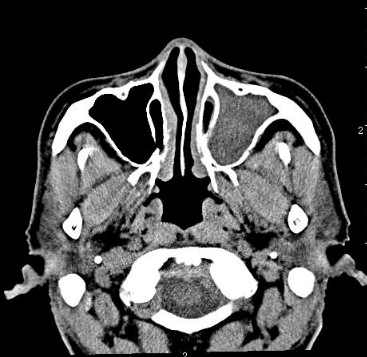

水平位:显示鼻窦的横向结构,有助于观察鼻腔和鼻窦的宽度。

鼻窦CT影像系统是一种高精度的医学成像技术,专门用于鼻窦区域的详细检查。这种系统通过计算机断层扫描(CT)技术,能够生成鼻窦区域的高分辨率图像,帮助医生准确诊断和评估鼻窦疾病。

总之,鼻窦CT影像系统通过高精度的成像技术,为医生提供了详细的鼻窦解剖和病变信息,是诊断和治疗鼻窦疾病的重要工具。